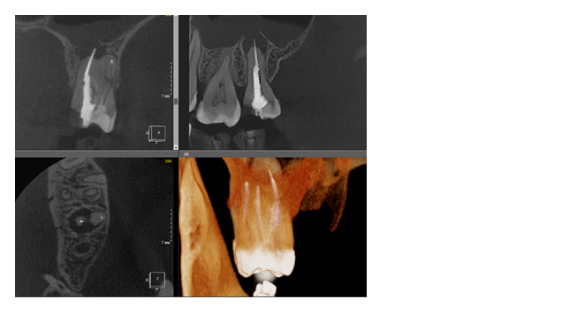

Рис. 1. Представлены два исследования (10x10 см и 20x20 см). На обоих изображениях хорошо видна канально-корневая система зубов, но, если масштабировать второе исследование, то качество неминуемо снизится, как и диагностическая эндодонтическая эффективность.

По сути воксель – это структурная единица изображения. Компьютерная томограмма состоит из вокселей, и их размер определяет качество снимка. Как правило, чем меньше FOV снимка, тем меньше и размер вокселя, а это, в свою очередь, делает изображение более качественным (рис. 3). Разные фирмы, производящие дентальные томографы пытаются конкурировать в размерах вокселя, особенно при больших зонах сканирования. Я стараюсь использовать два режима, как правило, это standart definition со средним размером вокселя и high definition с уменьшенным размером вокселя. Если намечается сложная эндодонтия, то, безусловно, high definition с минимальным значением вокселя будет крайне эффективно, но если у пациента огромное количество металла (циркон, металлокерамика и прочее) то порой именно стандартный размер вокселя помогает снизить количество артефактов и сделать изображение более читабельным.

Рис. 3. КЛКТ с зоной сканирования 5x5 см и размером вокселя 70 микрон.